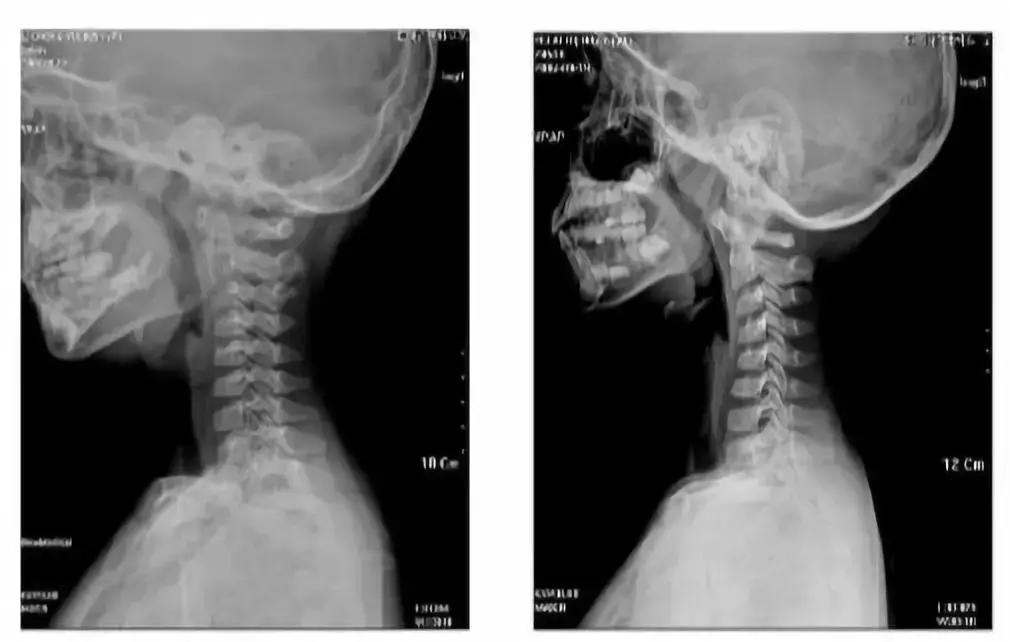

左:5岁孩子的颈椎生理曲度变直 右:7岁孩子的颈椎生理曲度呈“反弓”

颈椎反弓,指的是每个人的颈椎是有自然生理曲度的,长期低头会使颈椎的生理曲度发生变化,甚至向着反方向弯曲,形成“反弓”。

低头、坐姿不良的时间越长,对孩子的颈椎伤害越大,会出现颈椎自然曲度消失、变直或者反弓的情况,严重时还会出现寰枢关节半脱位。